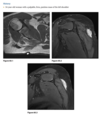

39 yo man fall

Axial T2 fat sat MR - bone contusions in medial patella and lateral femoral condyles (Arrows) with associated tear of medial retinaculum (Arrowhead)

Diagnosis: Acute patellar dislocation relocation

Occurs with internal rotation of femur on fixed and externally rotated femoral condyle - bone contusions on both.

Due to direct impaction, associated with ACL tears.

Radiographs = Lipohaemarthrosis or chip fracture adjacent to donor site of medial facet of patella.

MR findings = Disruption or sprain of the medial retinaculum, lateral patellar tilt or subluxation, lateral femoral condylar and medial patellar osseous contusions. Osteochondral injury to medial patella or lateral femur.